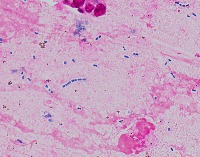

Medical Research: This model can be utilized in the field of medical microbiology and research to classify bacterial strains based on their visual characteristics in lab experiments and for the study of bacterial growth processes.

Healthcare Diagnostics: In healthcare, the "assembly" model could be used to assist in bacterial diagnosis in clinical lab settings, identifying the presence of specific forms of bacteria like Staphylococcus, Streptococcus, B-catarrhalis, Str_pne, and Enterococcus in samples.

Pharmaceutical Industry: The model could be applied in the development stages of antibiotics or bacterial treatments, helping to identify and study the response of specific bacterial strains to new drugs.

Educational Tools: Educators and students could employ the model as a learning tool for illustrating bacterial species classes, supplementing traditional teaching methods in biology or medicine related courses.